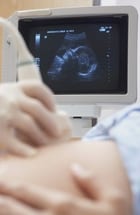

4-D ultrasound is performed in a physician's office or diagnostic imaging center, usually after 25 weeks of pregnancy. During the procedure, the technician applies a special gel, which helps to carry sound waves, to the patient's abdomen. The technician then holds the ultrasound probe against the abdomen in various places to capture a range of images. A computer produces the 4-D video (or DVD), which can be taken home by the patient. The procedure lasts about 30 minutes.